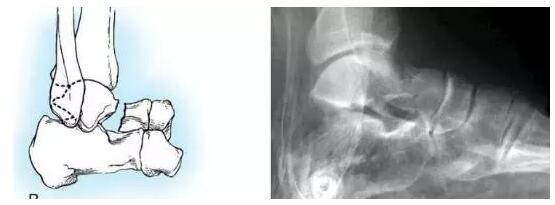

HawkinsⅡ型:距骨颈骨折移位伴距下关节脱位或半脱位